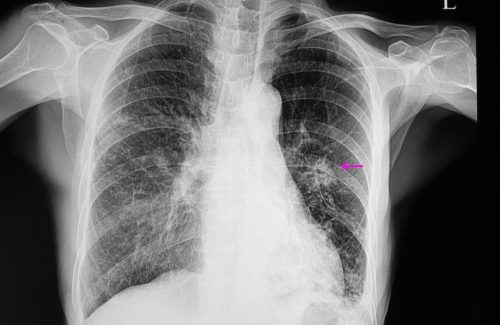

Akciğer kanseri teşhisi genellikle görüntüleme testleri (örneğin, bilgisayarlı tomografi veya BT taraması) ve biyopsi ile konulur. Tedavi seçenekleri tümörün tipine, evresine ve hastanın genel sağlık durumuna bağlı olarak değişir. Tedavi seçenekleri arasında cerrahi müdahale, kemoterapi, radyoterapi ve hedefe yönelik ilaç tedavisi bulunmaktadır. Erken teşhis, tedavi seçeneklerini ve hastalıkla başa çıkma şansını artırabilir.